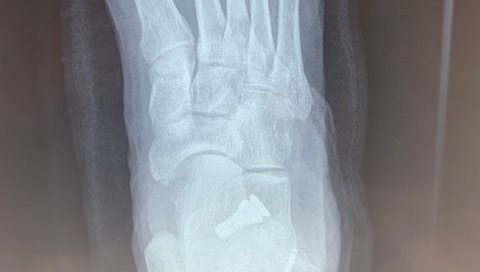

Gout

Blog's main page I have carried out surgery on three patients recently who have had moderate bunions on X-ray, however, clinically they appear to be much worse. On X-ray, you [...]